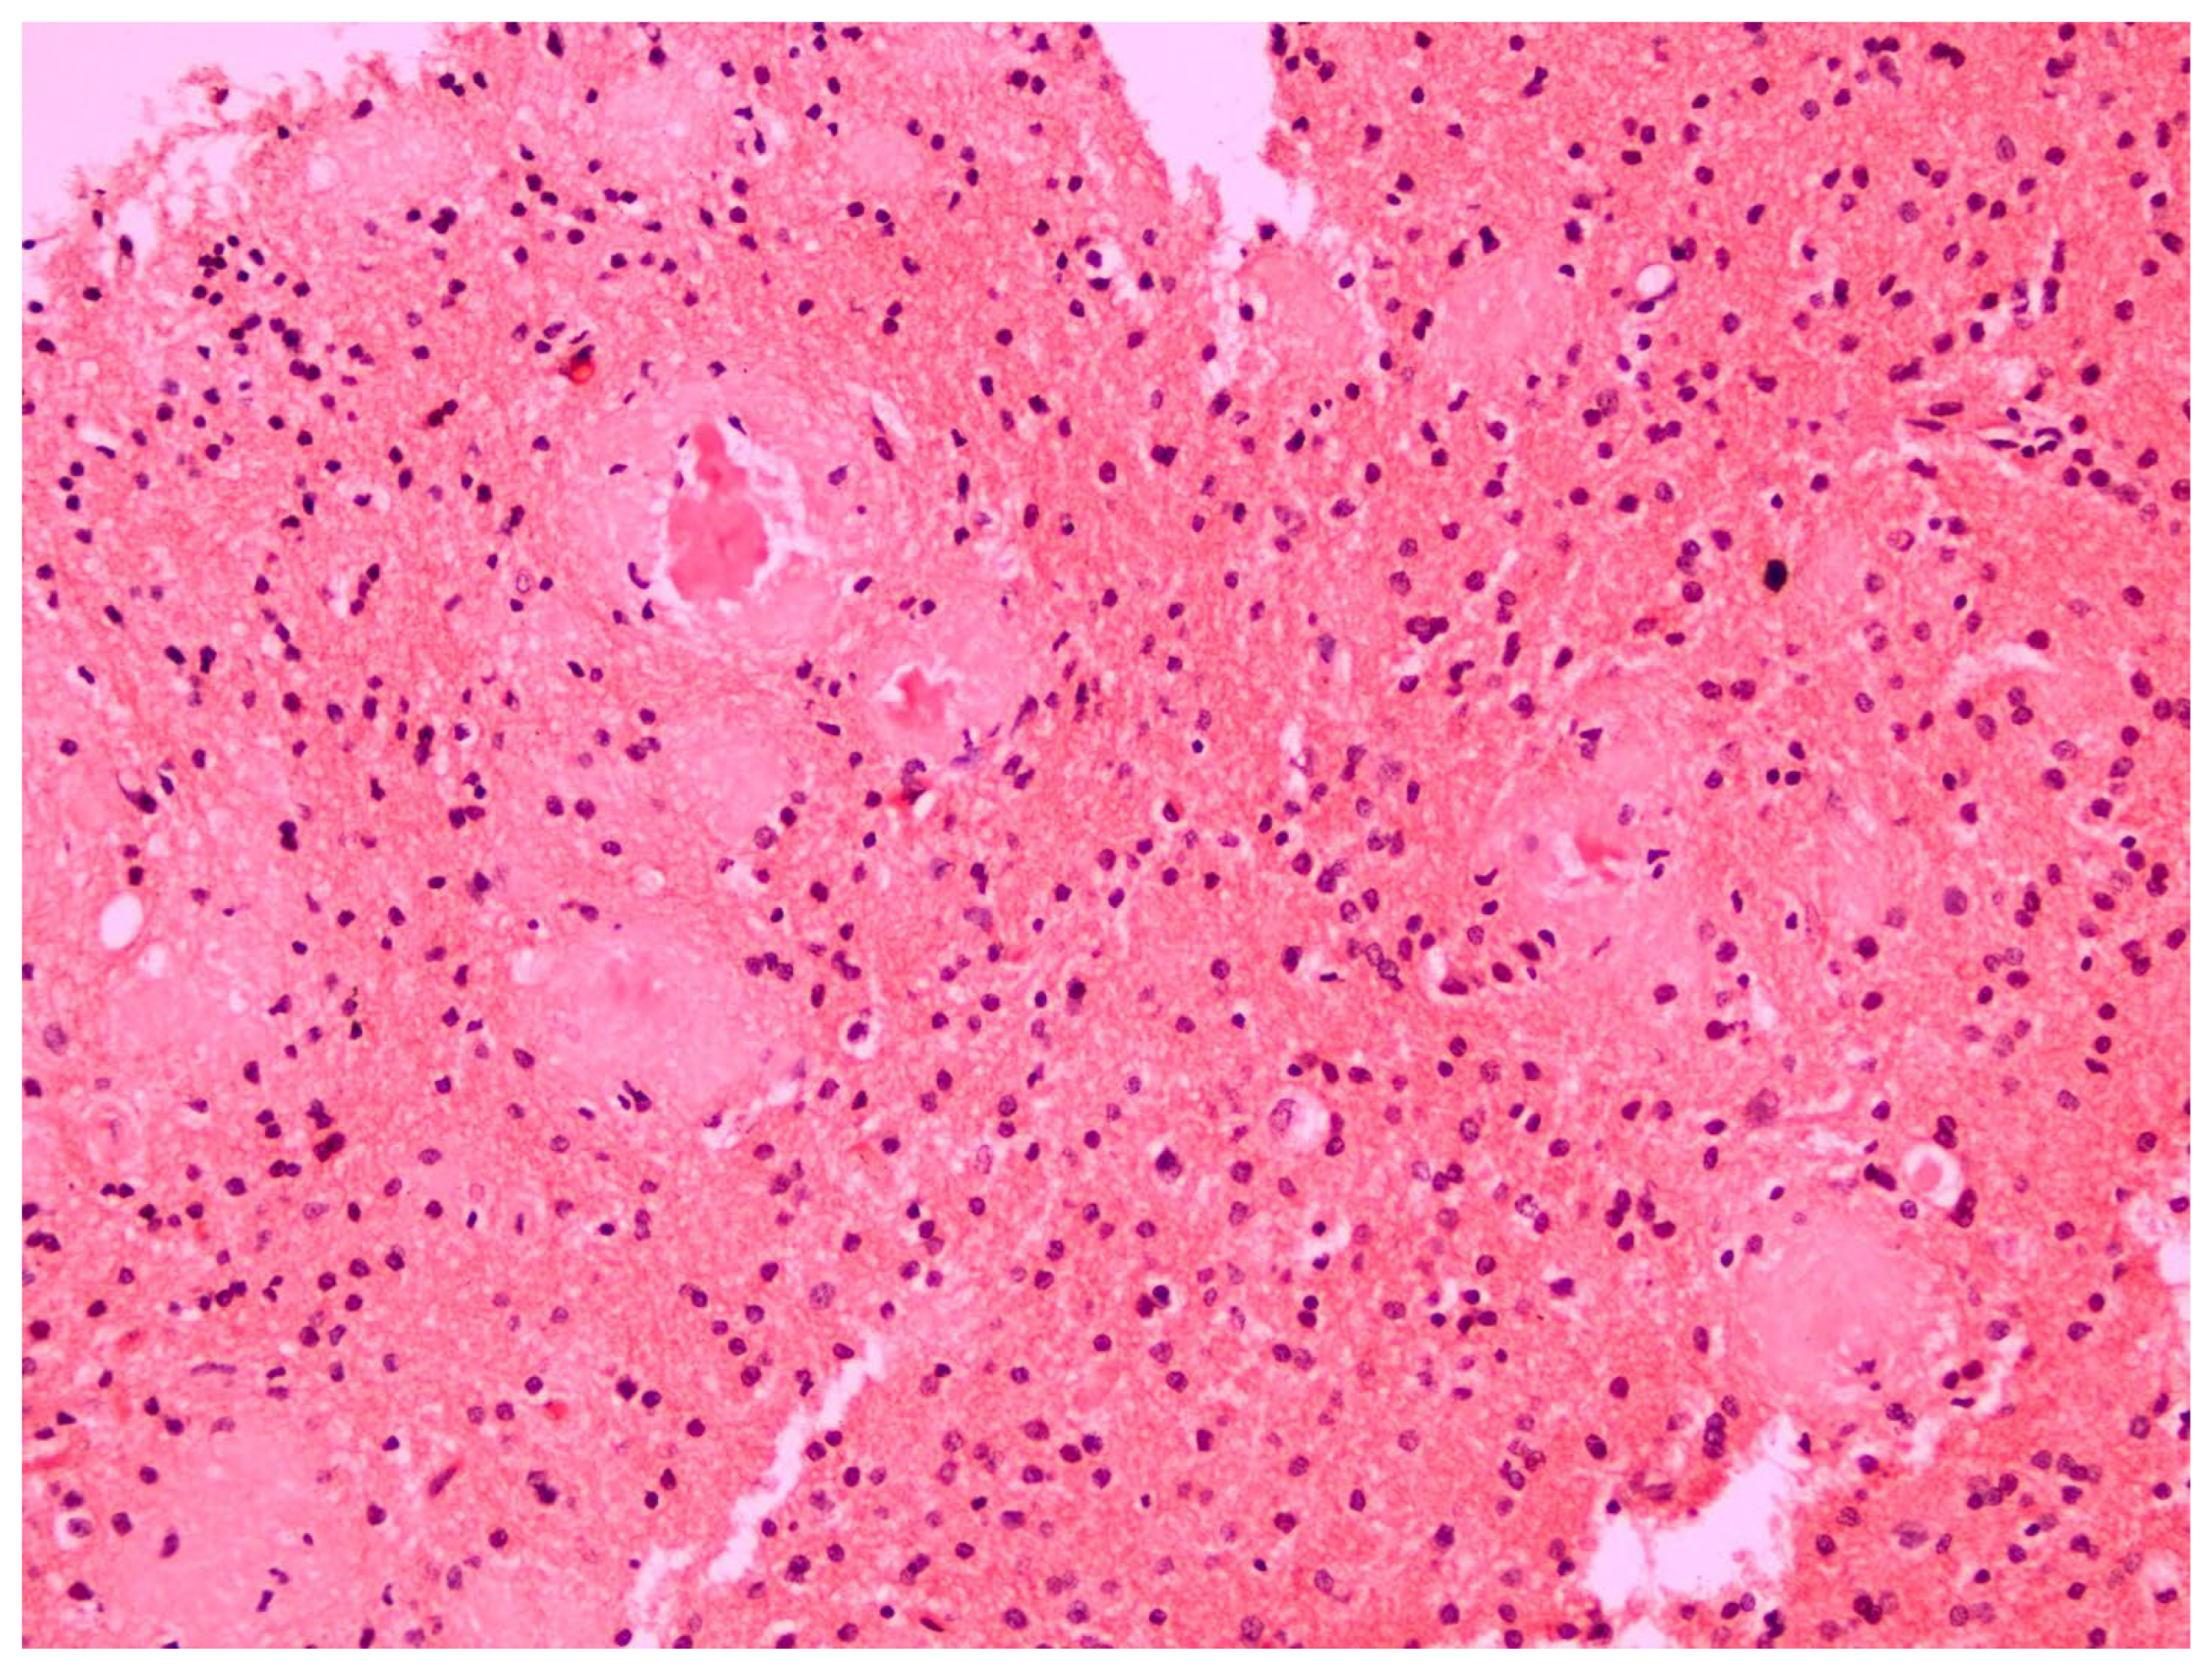

2. Case Report